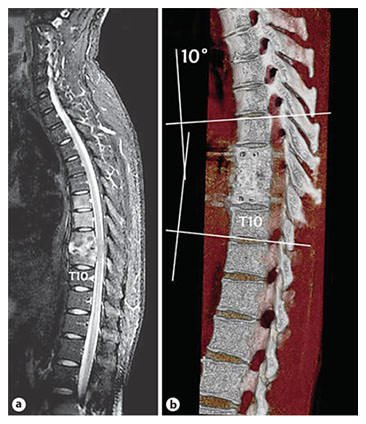

The typical site of involvement is the anterior aspect of the vertebral body adjacent to the subchondral plate and occurs most frequently in the lower thoracic vertebrae. A possible effect of this disease is vertebral collapse and when this occurs anteriorly, anterior wedging results, leading to kyphotic deformity of the spine. Other possible effects can include compression fractures, spinal deformities and neurological insults, including paraplegia.